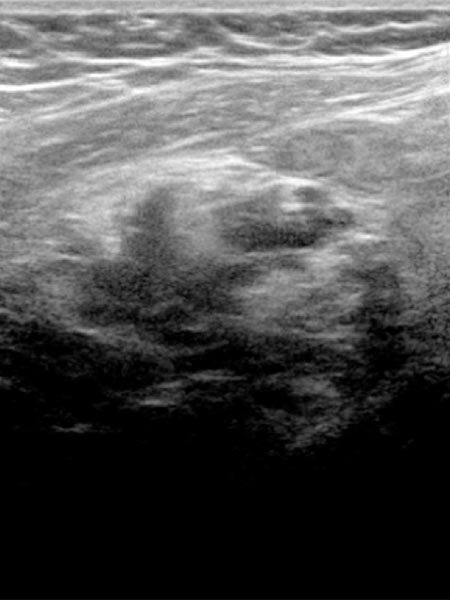

Pre-pregnancy ultrasound imaging with 10.4 MHz linear transducer. Evidence of an intramuscular subfascial venous malformation with multiple hypoechoic venous channels.